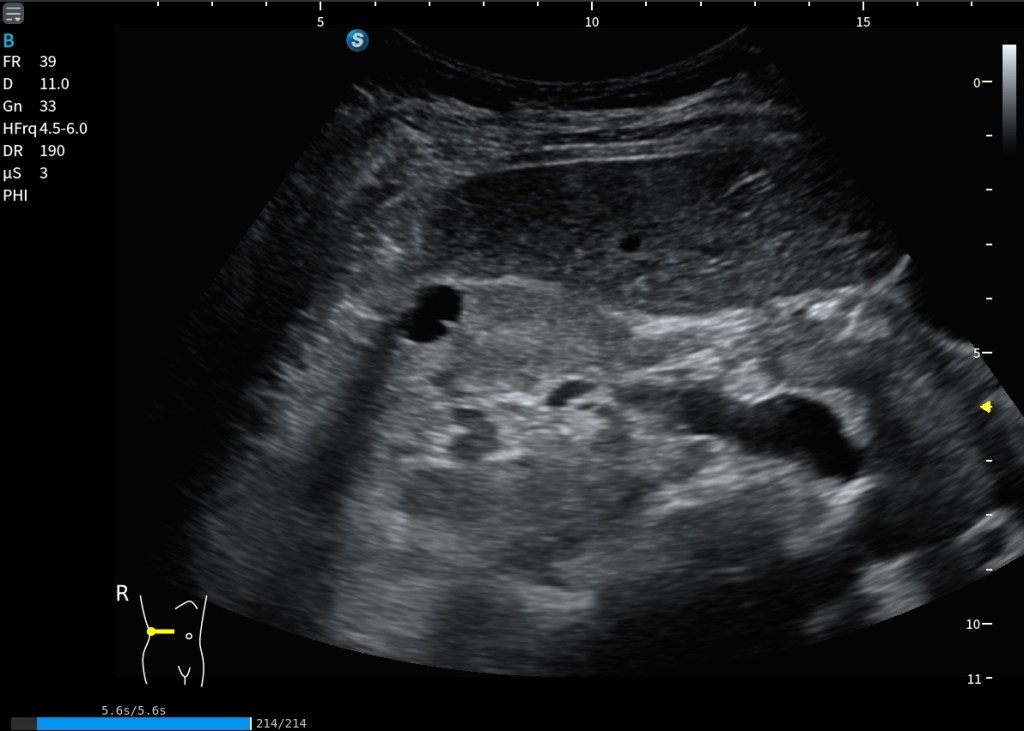

En la imagen siguiente, tenemos una inferior y una superior, en la superior estamos viendo una situación de normalidad. La corteza renal y el hígado se ven con la misma ecogenicidad. Es lo que buscamos siempre.

Sin embargo, en la imagen inferior la cosa cambia. Lo que observo es una hiperecogenicidad renal difusa del riñón derecho. El riñón se ve más brillante que el hígado de forma global, no es algo focal.

Está marcado con Normalidad y Patología.